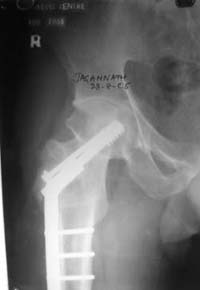

А третий вариант -- поправить и фиксировать закрыто? Ну что уж так сразу -- "реконструкция"! Звучит красиво, примерно как "реформирование системы здравоохранения", а если со стороны посмотреть -- перерубание живого с внедрением инородного. Зато снимок красивый будет -- почти как заграничный в этой же дскуссии, только без суставной щели, вот в чем беда, а так все класс...

При явно выраженном варусе и флексионных состояниях после сросшихся переломов шейки бедра у молодых рекомендуется реконструктивная операция по исправлению варуса для предотвращения раннего деформирующего артроза, приводящего в результате переднего импинжмента, как показано на снимке.

Межвертельная вальгусная остеотомия представляет наименьший риск среди всех реконструктивных операции в проксимальной части бедра, создавая наилучшие биомеханические условия (увеличивается сила абдукторов, увеличивается сила суставной реакции, уменьшение рычага моментов абдукторов и уменьшение скольжения) и при меньшем риске повреждения кровоснабжения головки, где обычно в 90% случаях достигается отличный результат при применении метода для лечения ложных суставов шейки бедра.

По моему, 120 градусная угловая пластина blade plate решит все проблемы, только необходим предварительный расчет угла остеотомии, и во время фиксации пластины не забыть латерализацию бедра, иначе ось конечности от варуса перейдёт в нежелательный вальгус.

Dynamic hip screw with abduction osteotomy with an additional cancellous screw

the best option is valgus osteotomy with DHS and also additional canceelous screw fixation. the idea is to convert vertical shear foeces to horriszontal

Stephen Kottmeier 17 Октябрь 2005, 21:05

and if viable follow with proximal valgus osteotomy

I think that this 31 yo deserves a try with valgus osteotomy, as so nicely illustrated by stephen kottmeier. However, I'd do it no matter what an MRI shows - thus why bother with the MRI? (What sort of data support MRI's ability to predict segmental collapse?)